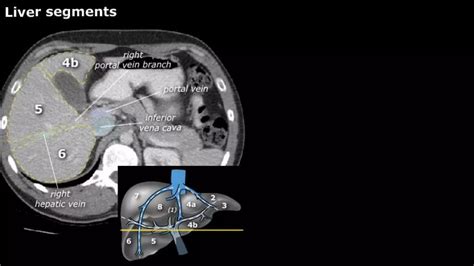

• Pre-surgical planning: Helping surgeons map out the liver's blood vessels and structural anatomy before procedures.

When a radiologist reviews the liver on CT, they look for specific "attentuation" patterns. Healthy liver tissue has a uniform appearance. Deviations from this indicate pathology. For example, fatty liver disease (steatosis) often presents as a darker, low-density appearance compared to the surrounding spleen or vessels. Conversely, iron overload (hemochromatosis) causes the liver to appear significantly brighter (more dense) on a scan.